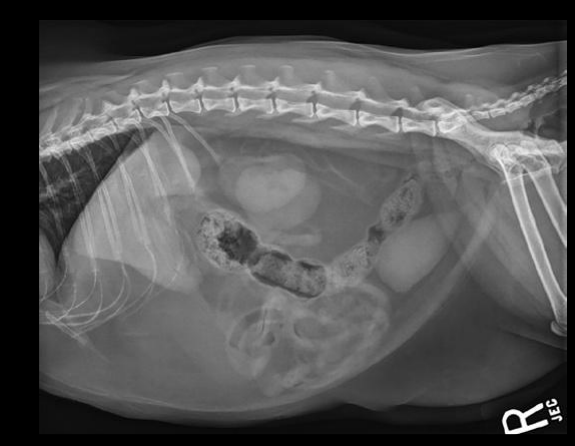

Radiografia laterolateral

Dependiendo de la posición los gases van a un lado o a otro: Decúbito lateral derecho Radiografía Lateral

- Gas en fundus

- Se ve mejor cola del bazo

- Mayor separación de siluetas renales

Decúbito lateral izquierdo

- Gas en píloro

- Mejor visualización delduodeno